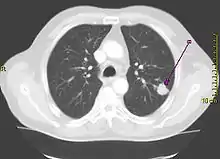

A chest X-ray showing a tumor in the lung (marked by arrow) | |

![]() | |